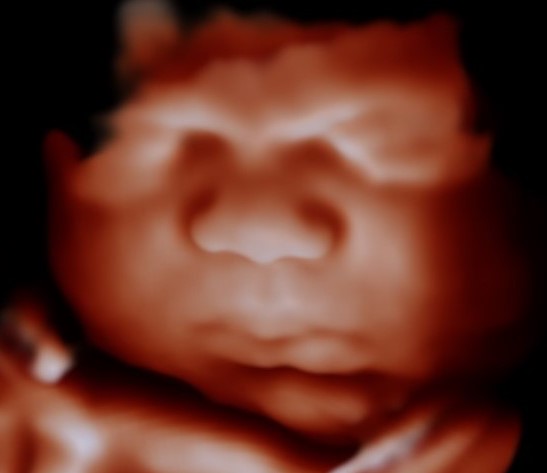

Our 4D TrueVue package offers a relaxed, heart-warming glimpse designed to help you truly be present with your baby. This comprehensive scan beautifully highlights your little one’s features in stunning detail, delicate fingers and toes, tiny ears, the soft suggestion of wispy hair, devoted to capturing that button nose, chubby cheeks, and pouty-lip moments you’ll treasure forever.

Perfect for regular little check-ins, it allows you to witness the beautiful changes unfolding as your baby grows and develops into the precious bundle you’re so eagerly waiting to meet.

Experience our exclusive most advanced ultrasound technology available. Our FirstView Evolution system delivers unprecedented image clarity and detail that sensitively transforms your scan into a soft, photo-style glimpse of how your baby may look at birth.

Using the precious details already captured on ultrasound, the curve of their cheek, their tiny nose, and delicate little features, our custom process carefully refines your image into a beautifully clear, detailed keepsake you can treasure. Then, with the support of precision-guided AI, we create a thoughtfully enhanced, true-to-life impression preview of the little face you’re so eagerly waiting to meet.